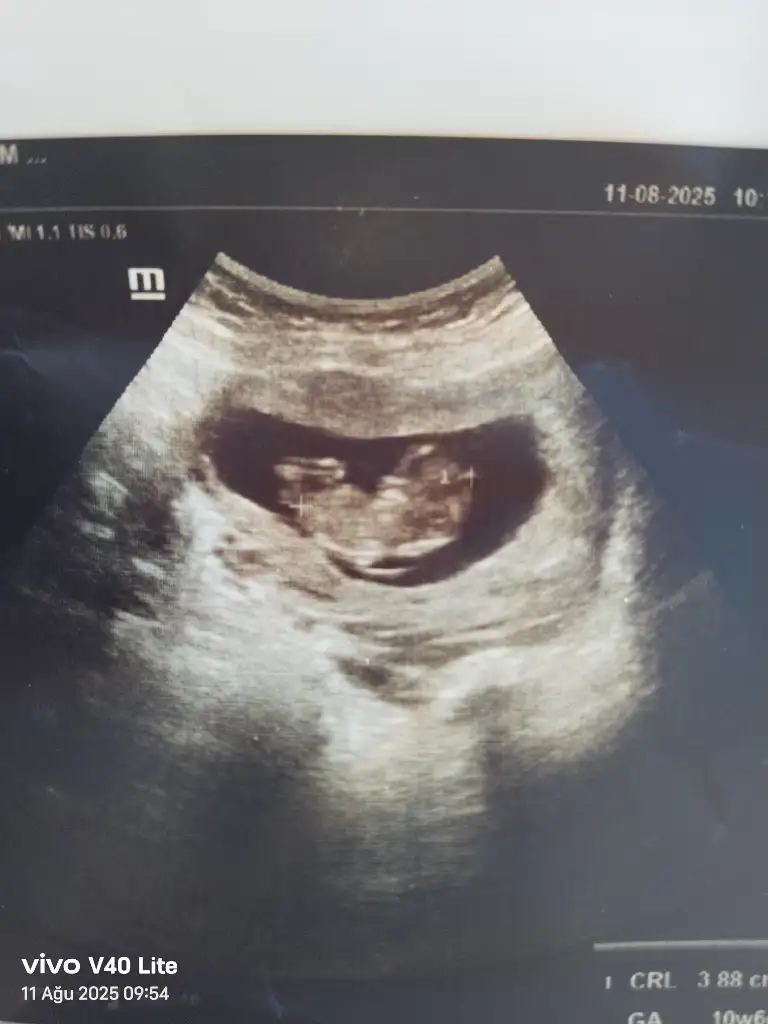

Merhaba hanımlar cinsiyet tahmini yapabilir misiniz 11 hafta

Eklentiler

• IMG_20250723_160814.webp

16,5 KB · Görüntüleme: 52

• IMG_20250723_160822.webp

13,9 KB · Görüntüleme: 50